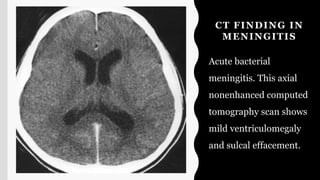

CT FINDING IN

MENINGITIS

Acute bacterial

meningitis. This axial

nonenhanced computed

tomography scan shows

mild ventriculomegaly

and sulcal effacement.